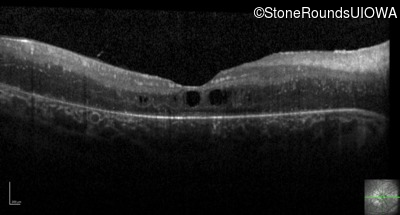

Optical Coherence Tomography - Left - 20/200

Exemplar / OCT Stack